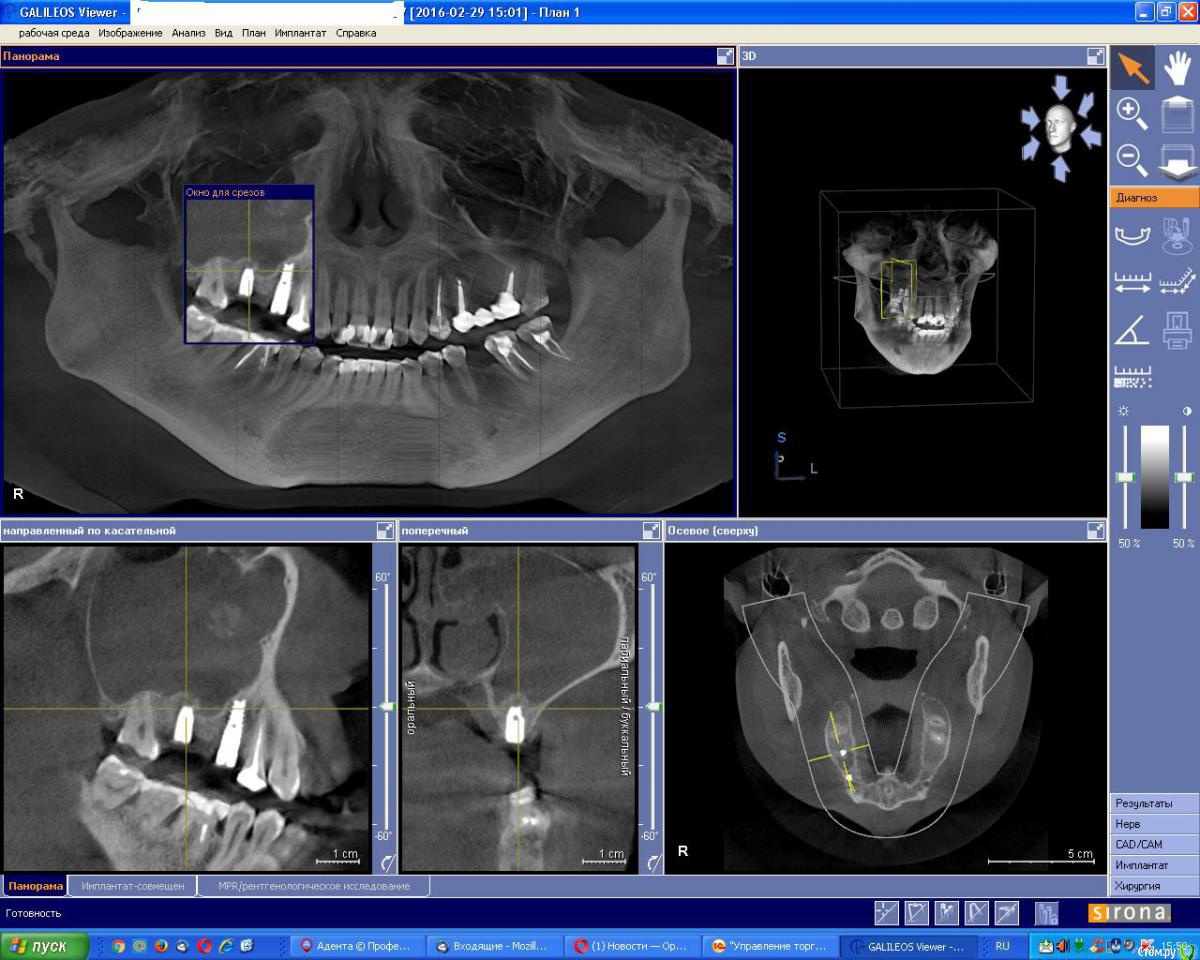

an_ver Опубликовано 26 января, 2017 Поделиться Опубликовано 26 января, 2017 (изменено) Фигня такая была...после синуса закрытого (наверно графт стрельнул), после долгих мытарств по Лорам, проколов и антибиотиков, залез сам, имплант удалил, графт выскоблил, все грануляции и хрень всякую почистил, в пазуху промыл стерильным физ.р-ом (долго,мыл), оросил дексой, в дыру пупочный шланг, детский))), конец наружу подшил ( 1см),чтоб не выскочил, и потом антибиотики внутрь, и мыть,мыть,мыть...физ.раствором,чтоб из носа побежало...на 3 -4 день, чистая вода побежала, на 7 скинул трубку, через 3 месяца вроде поставил шуруп, но рядом..и отстучался по Ильгаму,без графта...все хорошо Изменено 26 января, 2017 пользователем an_ver 3 Ссылка на комментарий

an_ver Опубликовано 26 января, 2017 Поделиться Опубликовано 26 января, 2017 История в картинках 4 Ссылка на комментарий